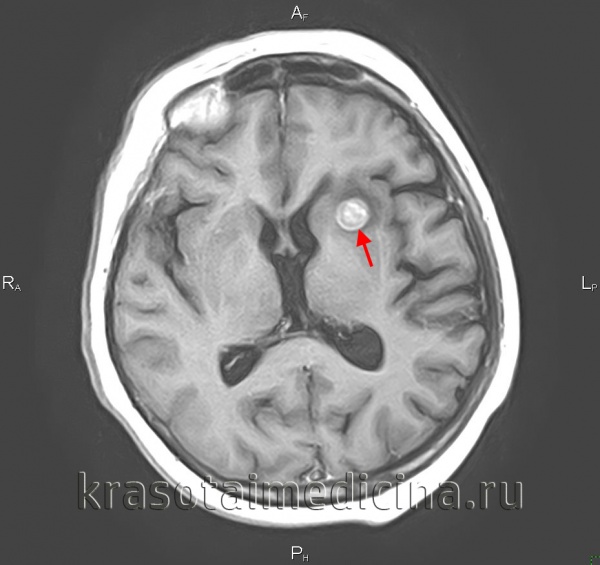

(а) МРТ, Т2-ВИ, аксиальный срез: у мужчины 58 лет, перенесшего два эпизода судорожных приступов, определяется неоднородно гиперинтенсивное объемное образование, инфильтрирующее базальные ганглии, вещество лобной доли, наружную капсулу и заднее бедро внутренней капсулы правого полушария.

(б) МРТ, постконтрастное Т1-ВИ, аксиальный срез: у того же пациента определяется несколько очагов контрастирования в центре объемного образования.

Основываясь на данной локализации (лобная доля) и отсутствии контрастирования обширных зон опухолевого поражения, наиболее вероятно, данная опухоль является вторичной МГБ. При биопсии было выявлено:

IDH 1 (+), EGFR(-), MGMT(+), р53 70%(+), PTEN25%(+) и MIB1 90%.